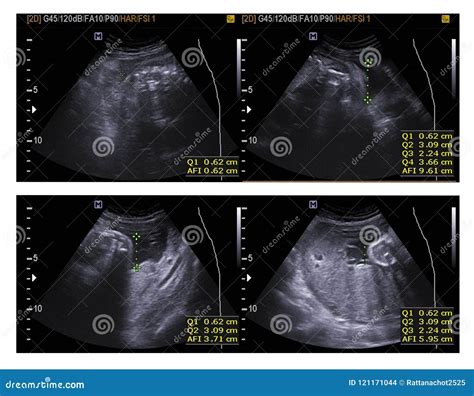

• Amniotic Fluid Levels: Checking the amount of amniotic fluid surrounding the baby.